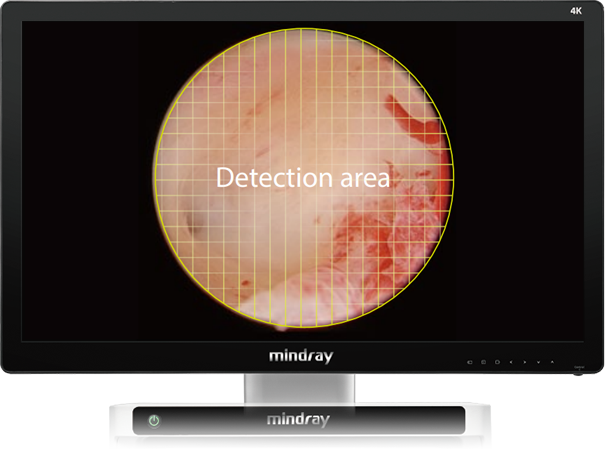

Automatic Scene Recognition, Intelligent Brightness Adjustment

Smart exposure: Determine different detection areas according to different scene and accurately match the exposure parameters without the need to manually switch department modes.

Small diameter scope scene (e.g. hysteroscope)